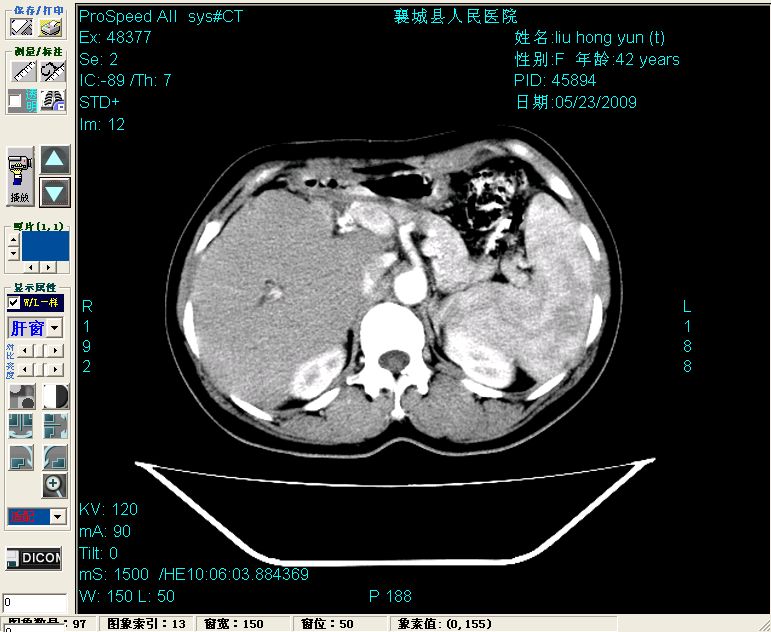

增强:

平扫左肝外叶体积显著减小,左肝外叶见多房囊性低密度区,左肝实质及右肝前叶浅表实质呈低密度改变,左肝及右肝前叶胆管扩张,脾大

增强动脉期前述低密度区轻度早其强化,门脉期强化程度显著增高,延期扫描强化程度下降,但仍为相对高密度影

胰头部见结节状高密度影,其前方略可分辨扩强胆部管,平扫到增强始终有,但现在尚难与胃肠造影剂鉴别.

结合病史考虑,1现在引起黄疸体征的原因应该是胆总管胰段结石阻塞,建议局部胃肠造影剂排空后复查.

2左肝及右肝前叶表现考虑胆囊摘除术后所致的肝动门脉瘘形成,慢性纤维组织炎性增生.不完全除外左肝胆管细胞癌

3脾大,可能与动门脉瘘所致门脉高压有关